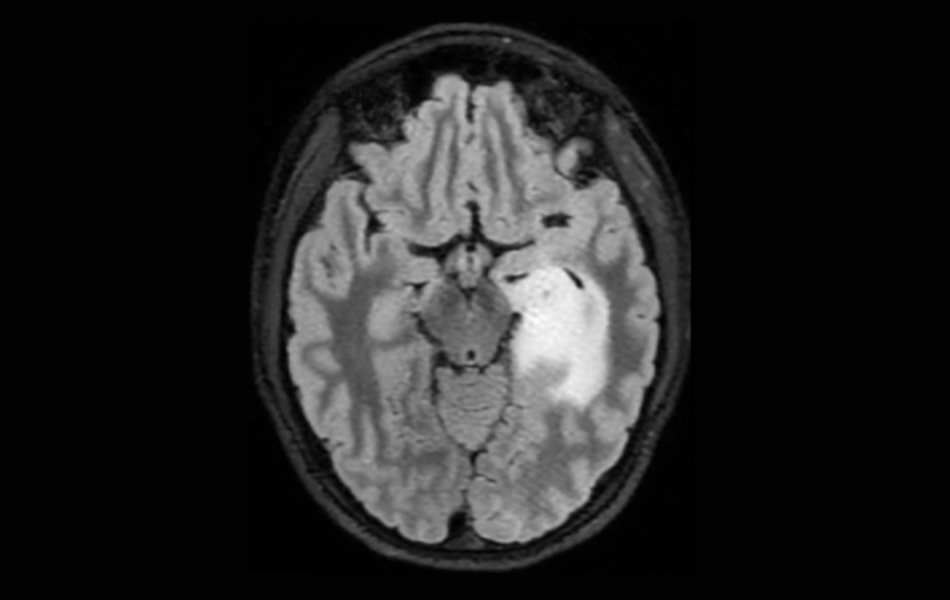

MRI scan of a low-grade glioma.

Now, an international study shows that adult patients with grade 2 gliomas can live longer if their surgeon performs a supramaximal resection, removing as much of the tumor as possible and beyond the margins visible on MRI scans.